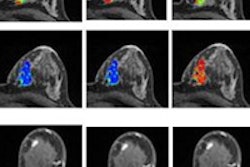

Because intensity values that are regularly used to analyze tissue vary by scanner, the Case Western team sought to apply a different approach for distinguishing between low- and high-risk cancers. They assessed the value of textural kinetics analysis, which measures dynamic changes in breast lesion texture during contrast uptake, for cancers considered to be low-risk (Oncotype DX recurrence score < 18) and high-risk (Oncotype DX recurrence score < 30).

The researchers found differences in gene expression that appeared as changes in tumor textural patterns on dynamic histograms. After quantitatively measuring these dynamic texture changes, they used the differences to determine which patients needed chemotherapy and which did not, according to the group.